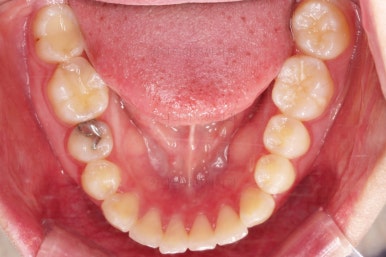

부산치아교정 이번 치료의 핵심인데요.

결손 부위에 미니스크류를 이용해서 뒤쪽 어금니들을 결손 부위로 앞으로 앞으로 계속 당겨줍니다.

얼굴모습에서의 중앙선도 지속저으로 체크하면서 한 쪽으로 치우침 없이 마무리를 해야 하고요.

틈새가 줄어들 때 까지 같은 작업을 반복합니다.

점점 틈새가 붙어가는게 보이죠?